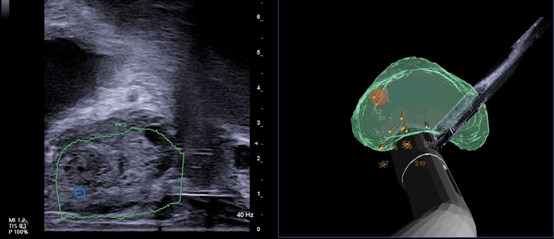

Una de las principales características de esta tecnología es la segmentación y sincronización automáticas de imágenes de RMN y US, realizadas mediante IA. Gracias a ello, el médico puede obtener una visión multimodal completa y en tiempo real, en una interfaz única e intuitiva. Esta integración no solo mejora la experiencia de uso, sino que también reduce la carga cognitiva del profesional, quien puede concentrarse plenamente en la atención al paciente.

El sistema incorpora además un seguimiento electromagnético de alta precisión, capaz de detectar en todo momento la localización exacta de la sonda. Con esta información, sincroniza las imágenes de resonancia con las de ultrasonido y permite identificar lesiones sospechosas en tiempo real. De esta manera, se mejora sustancialmente la exactitud en la toma de muestras, reduciendo el riesgo de errores y la necesidad de repetir procedimientos.